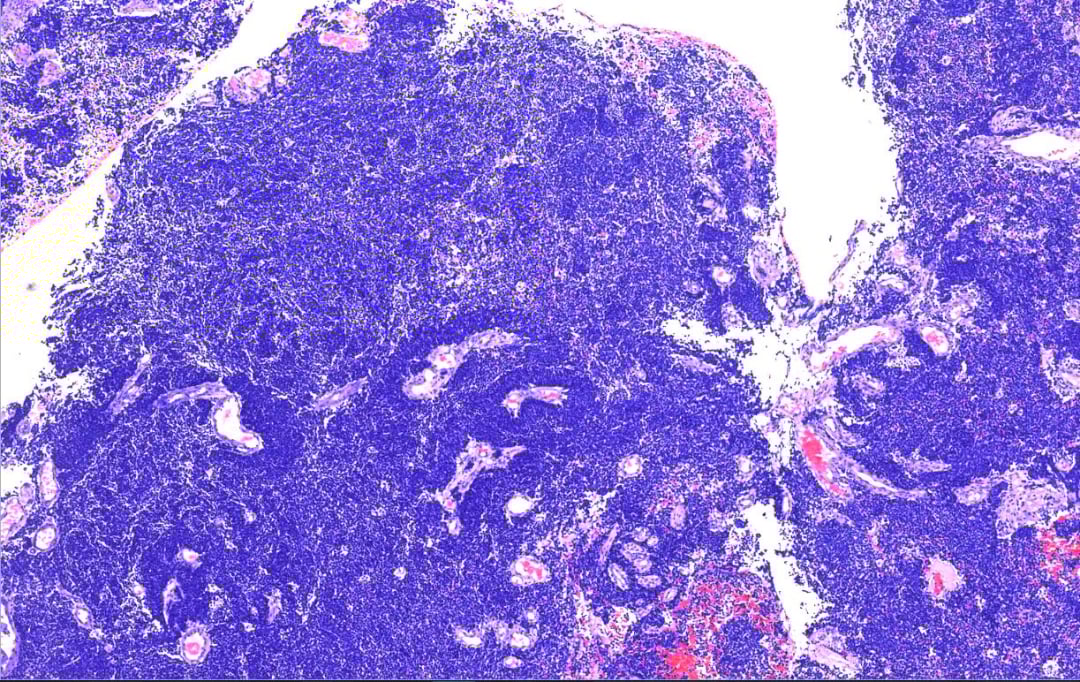

在显微镜下,肿瘤细胞位于正常的宫颈鳞状上皮下方,呈弥漫性浸润生长。这些细胞小而一致,细胞核大、细胞质少(高核浆比),核深染,排列成实性片状、巢状或梁状。此外,可见大量核分裂象和围血管生长,这些都是肿瘤侵袭性强的表现。

肿瘤位于正常宫颈鳞状上皮下方。

弥漫性浸润宫颈间质,呈实性片状,巢状及梁状排列,可见围血管生长。